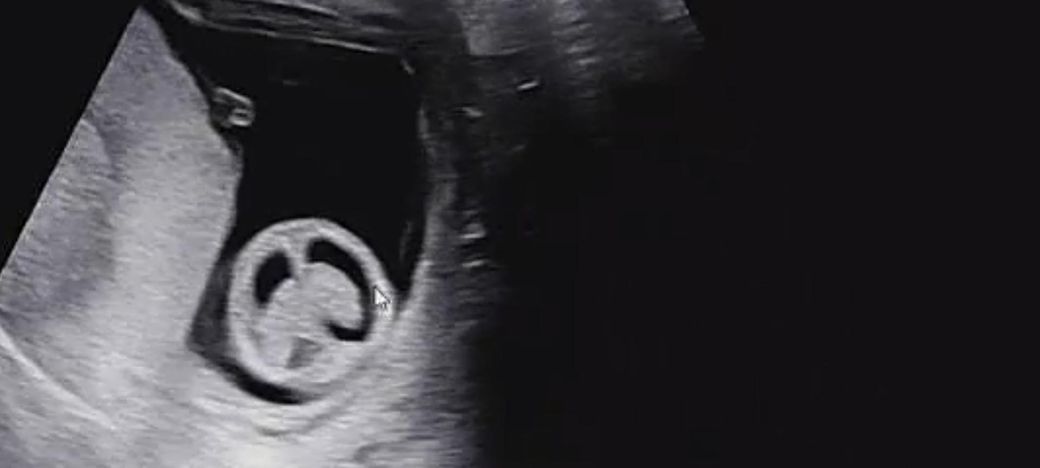

임신 12주차 태아 뇌 초음파 좀 봐주세요ㅜ

임신 12주차 이며 10주차 때 뇌 모양이 신경쓰인다고

12주차 태아의 뇌는 양쪽이 대칭인 나비 모양을 띠는 것이 아주 건강하게 잘 자라고 있다는 신호예요.

초음파상으로 뇌실의 모양이 고르고 깨끗하다면 대부분의 경우 발달이 정상적으로 이루어지고 있다고 보시면 됩니다.

다만 초음파는 각도에 따라 다르게 보일 수 있으니 담당 선생님의 소견을 믿고 마음을 편히 가지시는 게 좋아요.